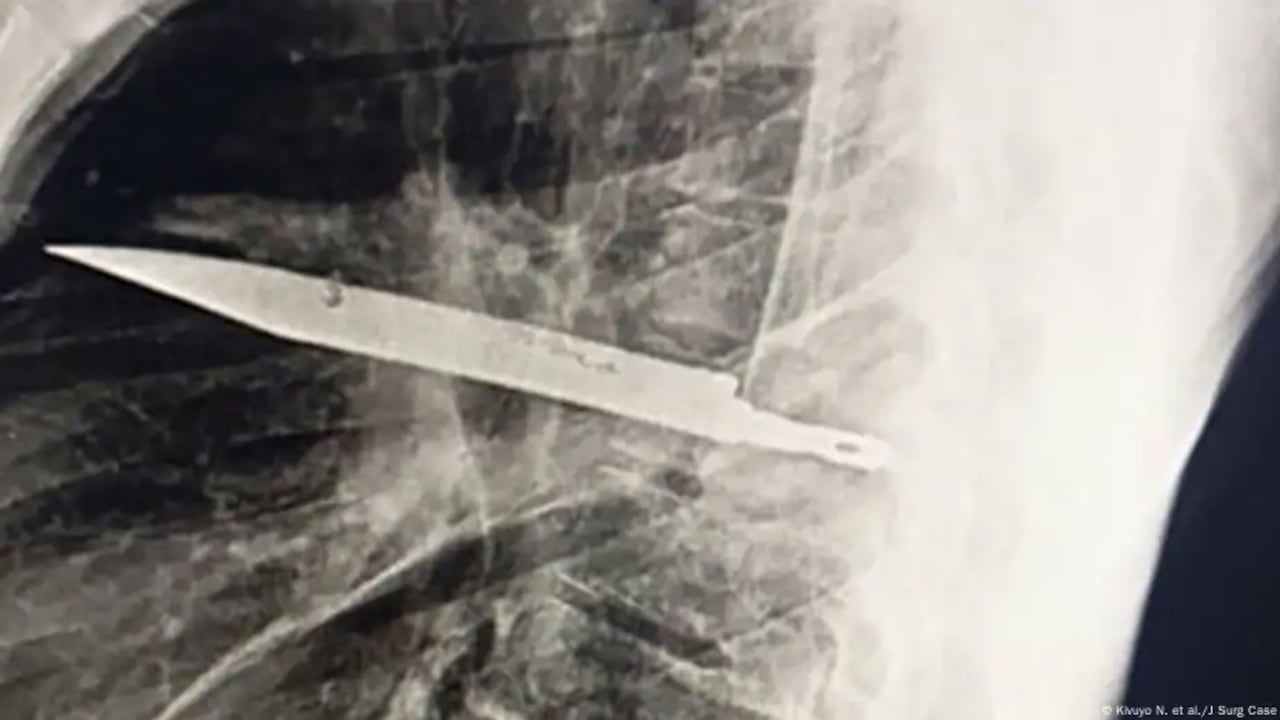

La radiografía realizada actualmente reveló un “objeto metálico retenido” dentro del tórax, pues una tomografía confirmó que se trataba de una hoja de cuchillo completa, incrustada desde la espalda hasta la parte frontal del pecho, rodeada de pus y tejido dañado.